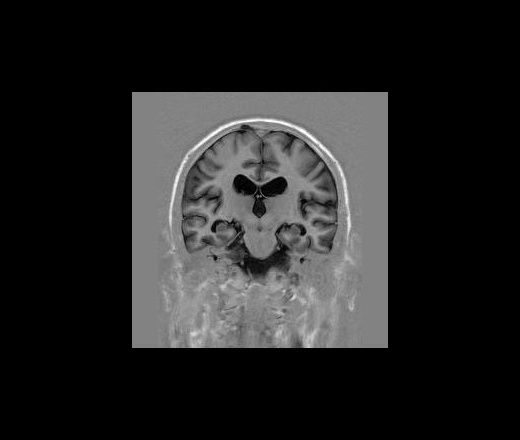

Пациент 35 лет, направлен неврологом из поликлиники с Ds: Рассеянный склероз? У данного пациента в течении года отмечается сильное головокружение и шаткость в походке, пришел на исследование на плечах у родственников. Данное исследование закачено на Dicom-сервер http: //www.radiomed.ru:8080/oviyam/oviyam? (под названием Brain-20101118).

Невринома правого слухового нерва

Если быть точным, VIII нерва;)

Более вероятнее невринома правого слухового нерва.